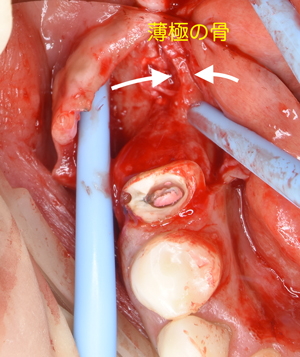

切開して開けてみると、2ヶ月前の抜歯跡が見受けられた。しかし

当院では骨の再生治療をインプラント移植時に同時進行で施しているので、全く問題はありません。

骨のない所に人工骨のβ–TCPを添加して、本物の骨に置換するのを待ちます。

歯肉をはく離すると、歯根は2分折されていました。同時に周囲の骨も大きく衰退していました。

また隣の歯のない部分の骨は、かなり菲薄していましたので骨幅を2倍に増幅させたのち、インプラントを

移植することにしました。